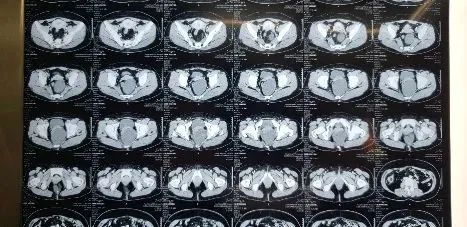

最近做了几例复发骶前囊肿患者,一些思考和总结分享给大家。

1.骶前囊肿容易当做妇科的卵巢囊肿误治,囊壁姑息切除。

2.这几例患者均为腹部开口或腹腔镜经盆腔入路,很难做到骶前囊肿的根部,导致囊壁残留。

对于切口与入路,部分与直肠关系不是很密切,体积不是很大的骶前囊肿可以经盆腔入路腹腔镜切除;少部分尾骨尖附近,体积小的骶前囊肿可以俯卧位骶前纵行切口入路切除。对于大多数体积比较大,且和直肠关系密切的骶前囊肿,我建议截石位,骶前尾骨前横弧形切口进行切除。